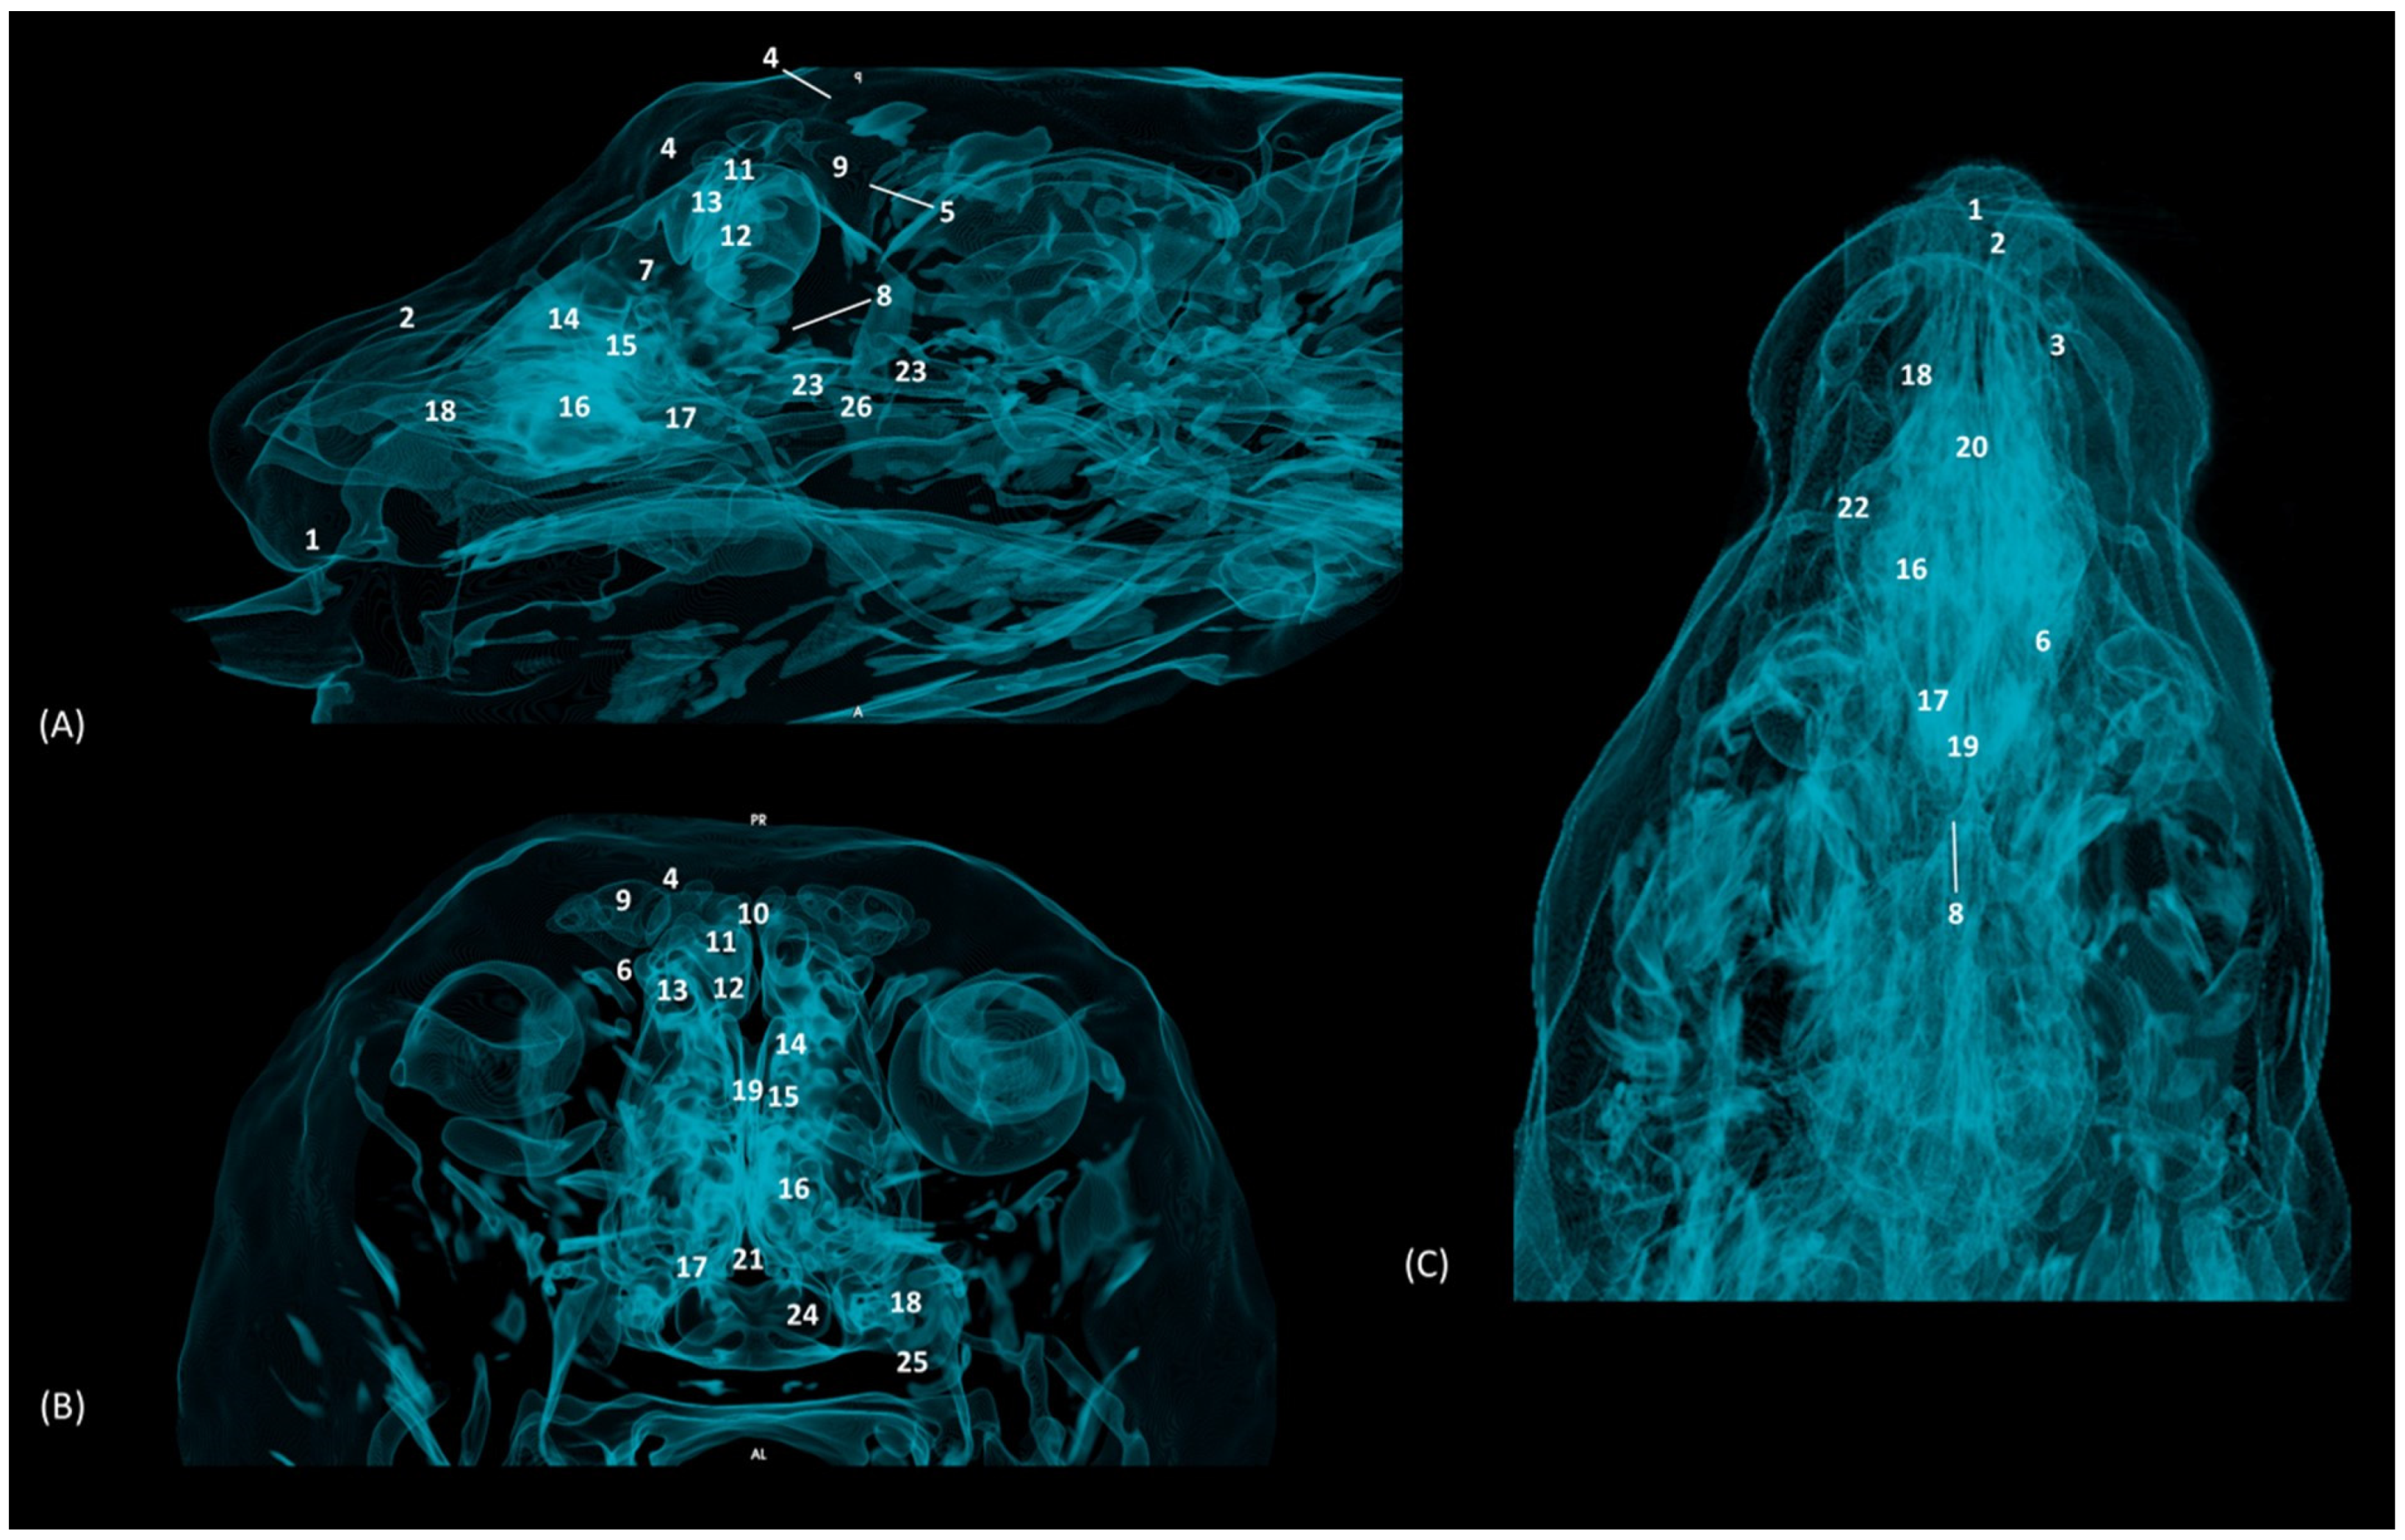

Finally, the MIP reconstruction of the domestic cat’s head is shown in Figure 30. The frontal sinus in this species, also proportionally large, deepens to more ventral levels than in the other felids. The ectoturbinates could also be clearly seen in the sagittal and transverse images. Both the path and the width of the nasopharynx (pars nasalis pharyngis) could also be observed extending caudal from the choana.

Figure 30. OsiriX MIP reconstruction images of the cat’s head. (A) Sagittal image. Left lateral view. (B) Transverse image. Caudal view. (C) Dorsal image. Dorsal view. 1. Incisive bone; 2. Nasal bone; 3. Maxilla; 4. Frontal bone: external plate; 5. Frontal bone: internal plate; 6. Frontal bone: orbital surface; 7. Ethmoid bone: tectorial plate; 8. Ethmoid bone: cribriform plate; 9. Frontal sinus; 10. Frontal sinus: septum; 11. 1st ectoturbinate. 12. 2nd ectoturbinate; 13. 3rd ectoturbinate; 14. Dorsal nasal concha; 15. Middle nasal concha; 16. 3rd endoturbinate; 17. 4th endoturbinate; 18. Ventral nasal concha; 19. Nasal septum: ethmoid bone (perpendicular plate); 20. Nasal septum: cartilage; 21. Vomer; 22. Zygomatic bone: body; 23. Sphenoidal sinus; 24. Choana; 25. Palatine bone: horizontal and perpendicular plate; 26. Presphenoid bone.